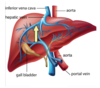

Following placement of the device in the image, the distal balloon is MOST likely to occlude the:

hypopharynx.

esophagus.

mainstem bronchus.

trachea.

Esophagus

Explanation:

The Combitube is a supraglottic, double lumen device that is blindly placed in the hypopharynx. The proximal balloon occludes the hypopharynx, while the distal balloon occludes the esophagus.

If the tip is placed in the esophagus (this is common), the lungs can be ventilated through the lumen between the distal and proximal balloons.

It is uncommon that the tip is positioned in the trachea, but if you get lucky, the distal lumen can be used for ventilation.

Pathology at or below the larynx may render this device useless. Esophageal rupture has been reported. Cricoid pressure should be released (not maintained) when placing the Combitube.

This is not a double lumen endotracheal tube!